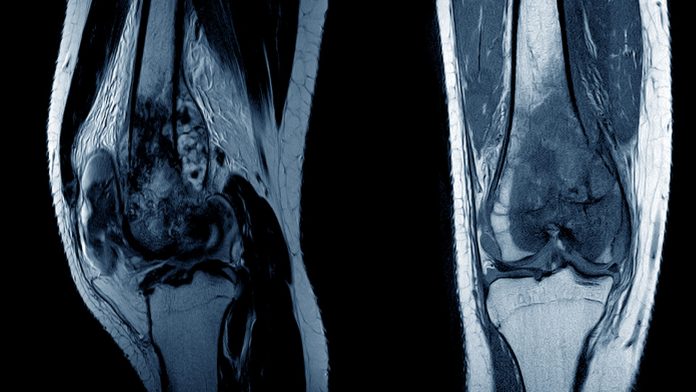

Osteosarcoma, a primary malignant bone tumour, poses a significant challenge in oncology due to its complex pathogenesis and often aggressive nature. Osteosarcoma primarily affects the long bones of adolescents and young adults, thus presenting unique clinical and therapeutic considerations.

It accounts for approximately 5% of childhood tumours. More than 50% of these tumours in children and adolescents arise from the long bones around the knee. Osteosarcoma is rarely seen in soft tissue or visceral organs, and there appears to be no difference in presenting symptoms, tumour location, and outcome for younger patients (<12 years) compared with adolescents.

As the most common primary bone cancer in children and adolescents, understanding its complexity and evolving treatment strategies is paramount for improving young patient outcomes and their quality of life.